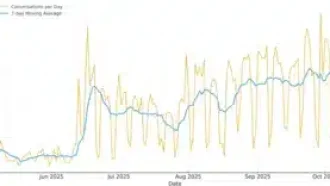

برای اینکه نتایجشون دقیقتر باشه، شرکتکنندهها باید هر روز احساساتشون (مثلاً چقدر ناراحت یا پراسترس بودن) رو با موبایل توی یه فرم سریع ثبت میکردن – به این میگن Ecological Momentary Assessment یا EMA یعنی ارزیابی لحظهای با اپلیکیشن موبایل. بعدش هم یه حلقهی هوشمند به اسم Oura به دستشون بوده که به طور مداوم ضربان قلبشون رو ضبط میکرد؛ خلاصه از هر دو جنس داده جمع میکردن: هم حسی، هم عددی.

حالا نکتهی جالبی که پیدا کردن این بود: توی روزهایی که خانومهای باردار خیلی استرس یا اضطراب داشتن، با هر هزار قدم اضافه (یعنی هرچی بیشتر راه میرفتن)، HRV شبشون تقریباً ۳/۵ درصد بیشتر میشد. یعنی انگار بدنشون بهتر با فشارهای عصبی کنار میومد، اونم فقط با کمی فعالتر بودن! این نتیجه خیلی معنیدار بوده (برای دوستای آمار دوست: P-value کمتر از 0.001، یعنی مطمئن بودن تصادفی نیست!).

ولی یه نکتهی باحالتر: تو روزهایی که حالشون معمولی یا خیلی خوب بوده (نه استرس خاصی نه ناراحتی)، این افزایش HRV با فعالیت بدنی تقریباً صفر یا خیلی کم بوده. یعنی مثلاً اگر اضطراب کم بوده و هزار قدم اضافه راه میرفتن، خیلی تغییر قابلتوجهی توی بدنشون اتفاق نمیافتاده.